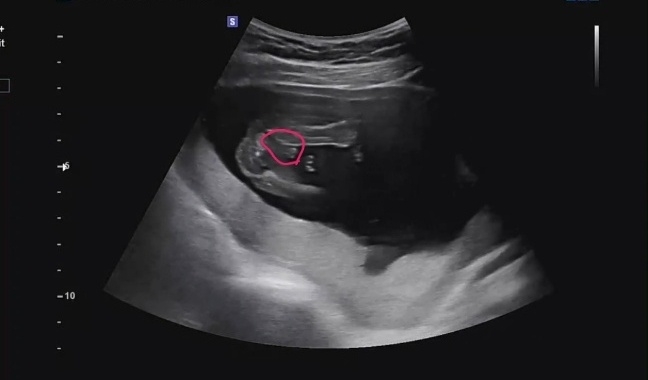

저도 아들맘 확정받고 왔어요!

16주 5일차고 선생님이 시크한 편이라 초음파 볼 때에 슉슉 지나가길래 혼날 각오하고 '지금은 성별 안 알려주시죠..?' 했는데 다리 사이에 뭐 있는데 못 봤냐고 하시더라구요 😂 집에 와서 영상 돌리고 돌리다가 겨우 확인했어요! 너무너무 신기한게 아들이란 느낌이 계속 오긴 했었거든요~ 태몽, 꿈에서 나오는 애기 모습, 먹는 건 전부 딸이었는데 얼굴, 등 피부도 다 뒤집어지고 임신선이 똑바로 일자로 진해지는 것 같아서 혹시? 했는데 역시네요~ 게다가 저는 뽀글뽀글 태동도 15주 초 부터 느꼈어요!